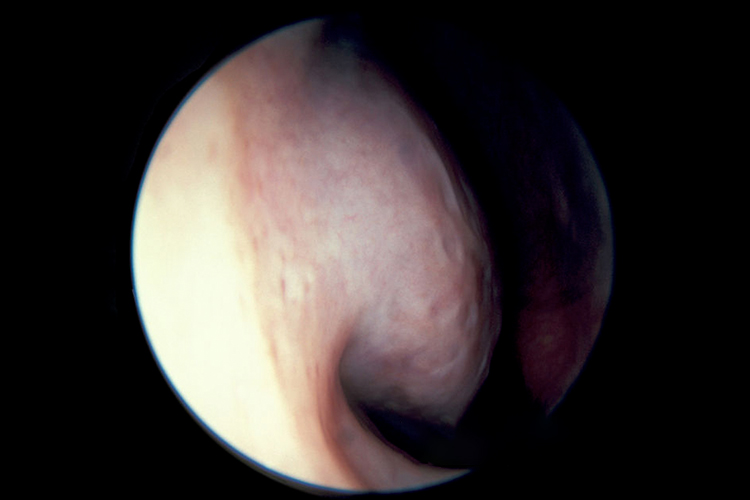

临床以反复鼻痒、喷嚏、鼻塞和水样涕症状为主,在接触变应原后或睡眠时加重,起床及活动后减轻;鼻腔检查时可见鼻甲苍白、水肿,鼻腔有较多稀薄黏液样鼻涕。

疾病无症状期间,鼻黏膜大多为正常,但发病期间患者的鼻黏膜可呈苍白、充血样或淡蓝色,通常为高度水肿,以下鼻甲更为明显。